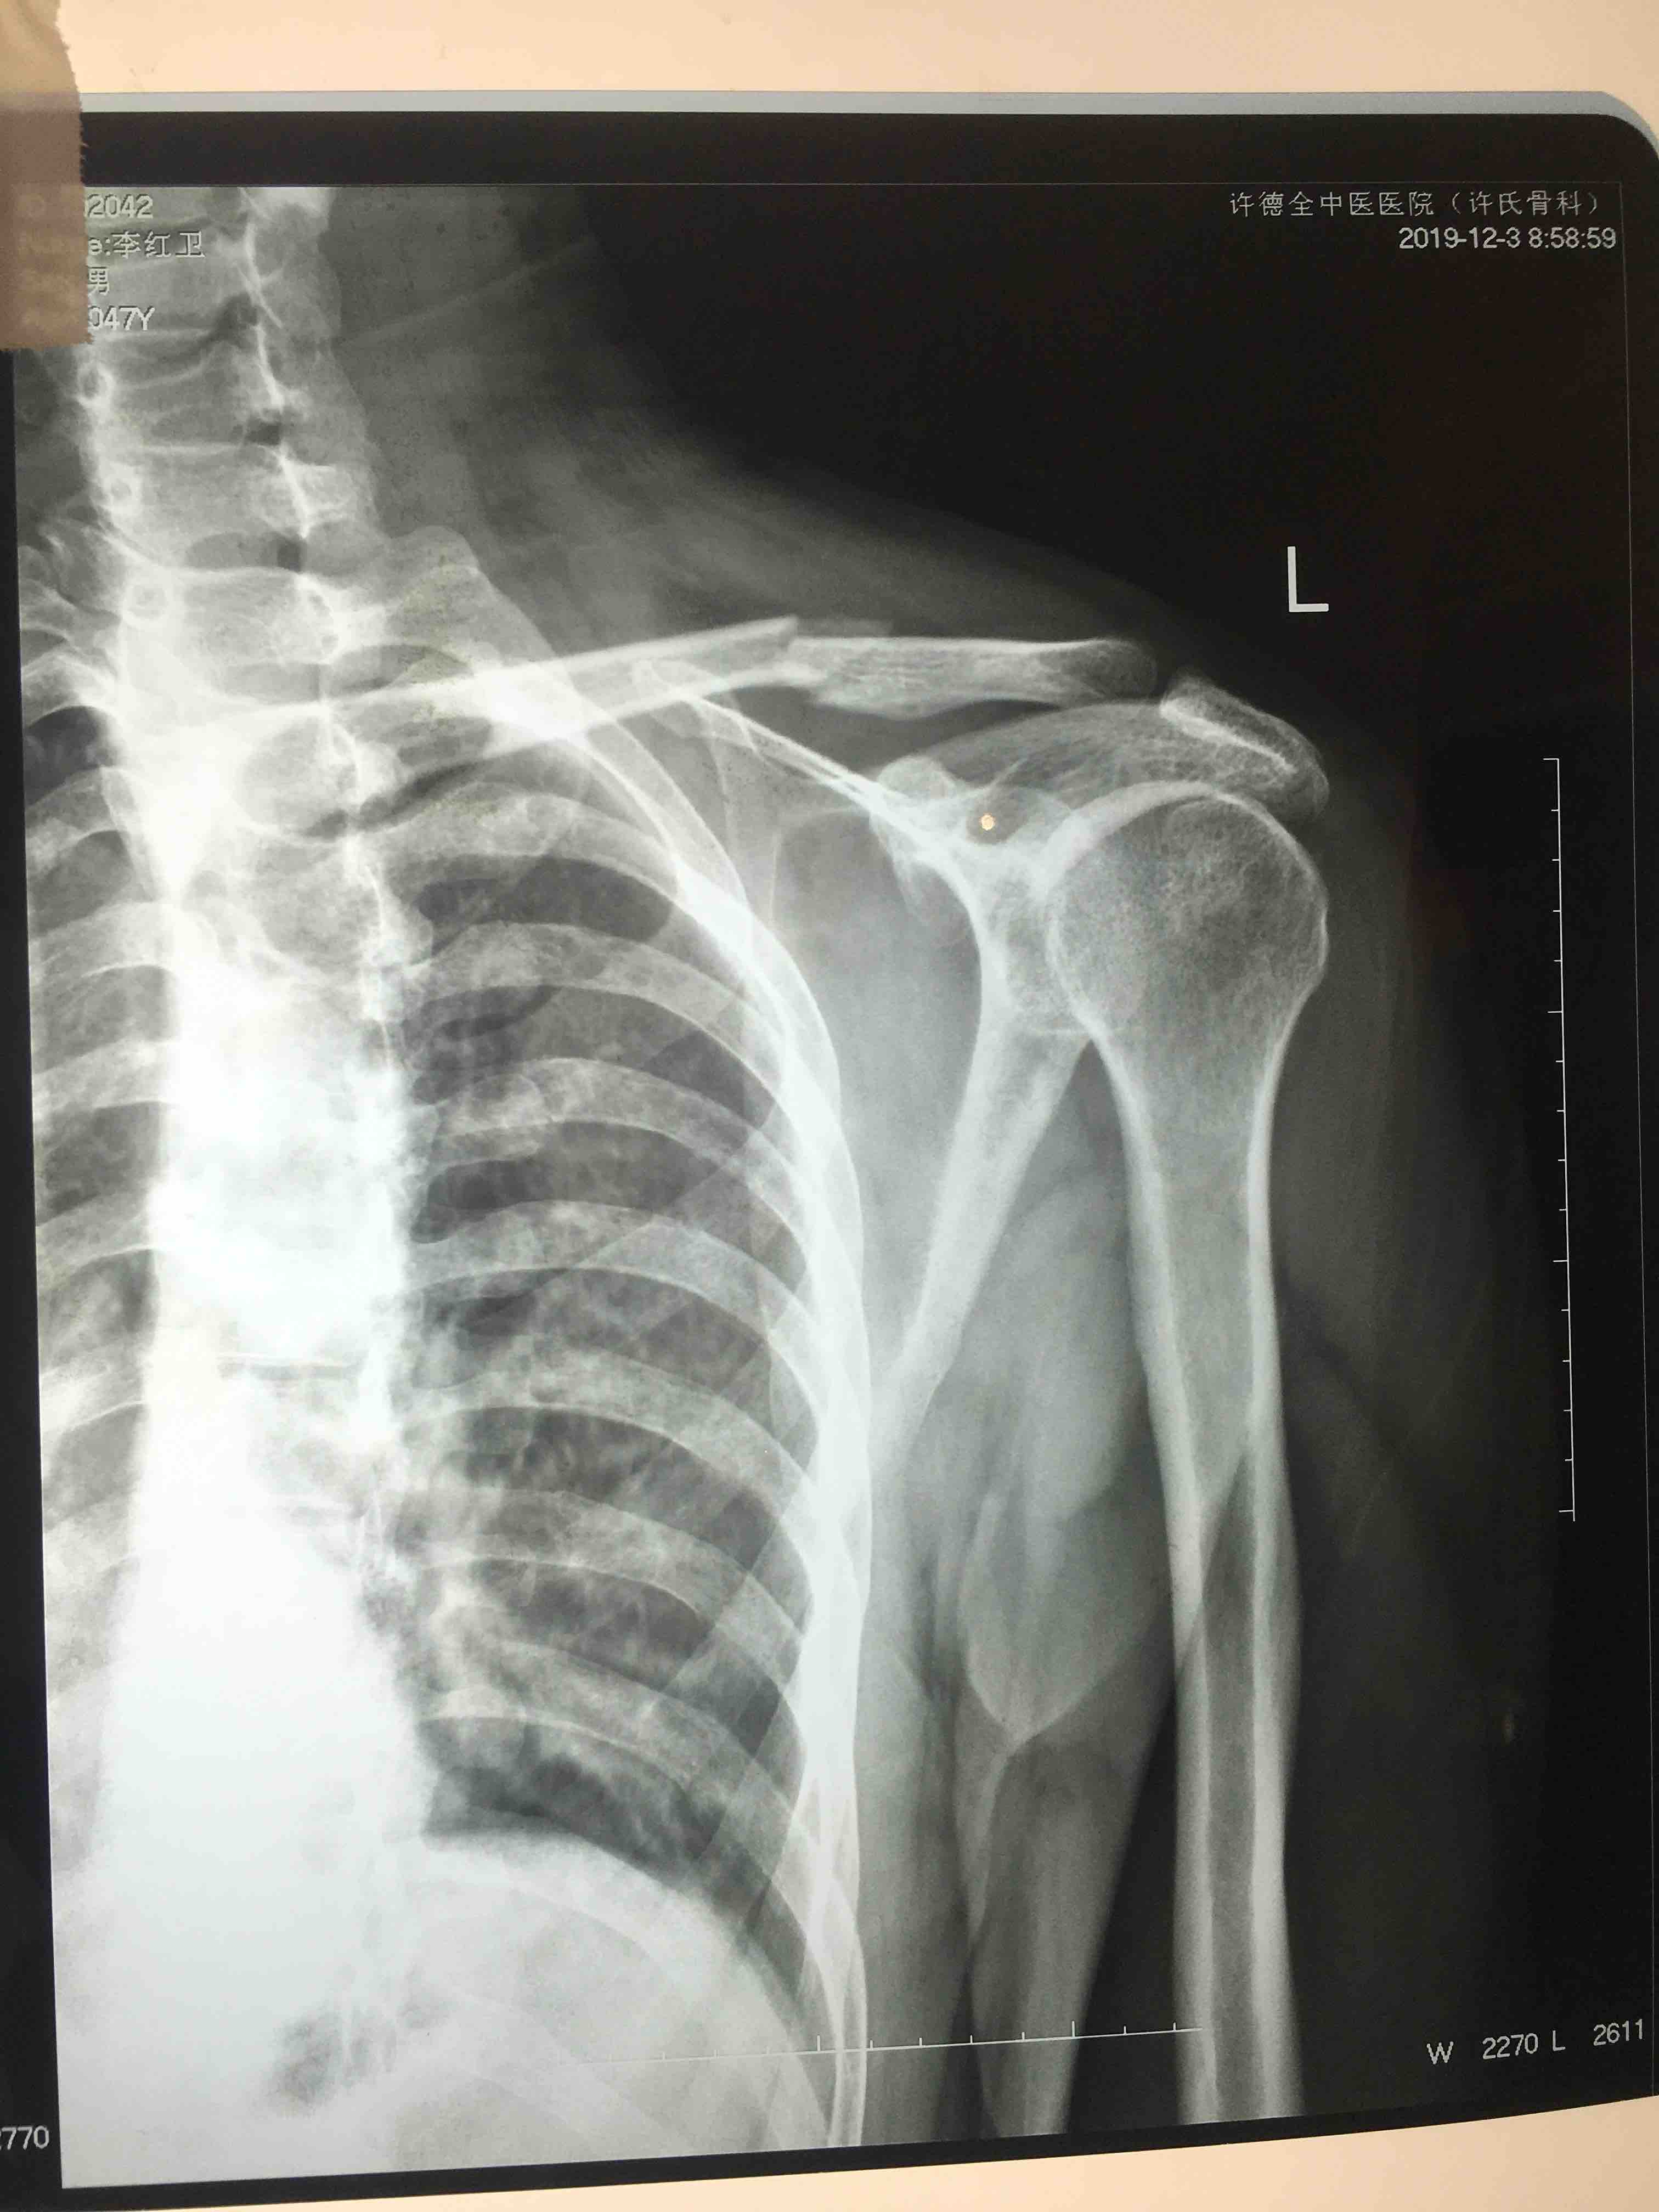

锁骨骨折(切复内固定术)

骨折 锁骨骨折

摔伤后左肩肿痛,活动受限1小时入院。既往身体健康,无不良嗜好。

生命体征平稳,心肺复未见异常。左肩部皮色皮温正常,压痛及纵向叩击痛阳性,肩关节活动受限,末梢血运感觉正常。

诊断左锁骨骨折在臂丛麻醉下切复内固定术,术后抗炎消肿等处理。